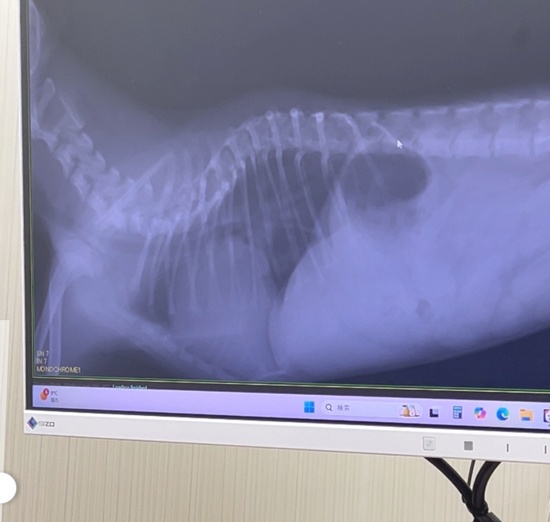

これが正常な犬の胸椎だとすると

下がアディルのです。椎骨が腰の方側(右側)は普通の形ですが、首側に向かって潰れたような形になってます。

もう、どうなっちゃってるの?というような形です。